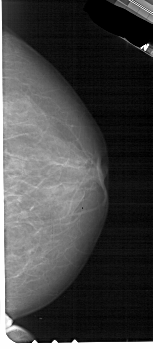

A_1839_1.RIGHT_MLO

RIGHT_MLO LINES 5491 PIXELS_PER_LINE 2791 BITS_PER_PIXEL 12 RESOLUTION 43.5 NON_OVERLAY